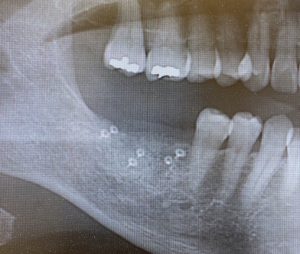

当院での骨造成の症例です

骨造成直後のレントゲン写真